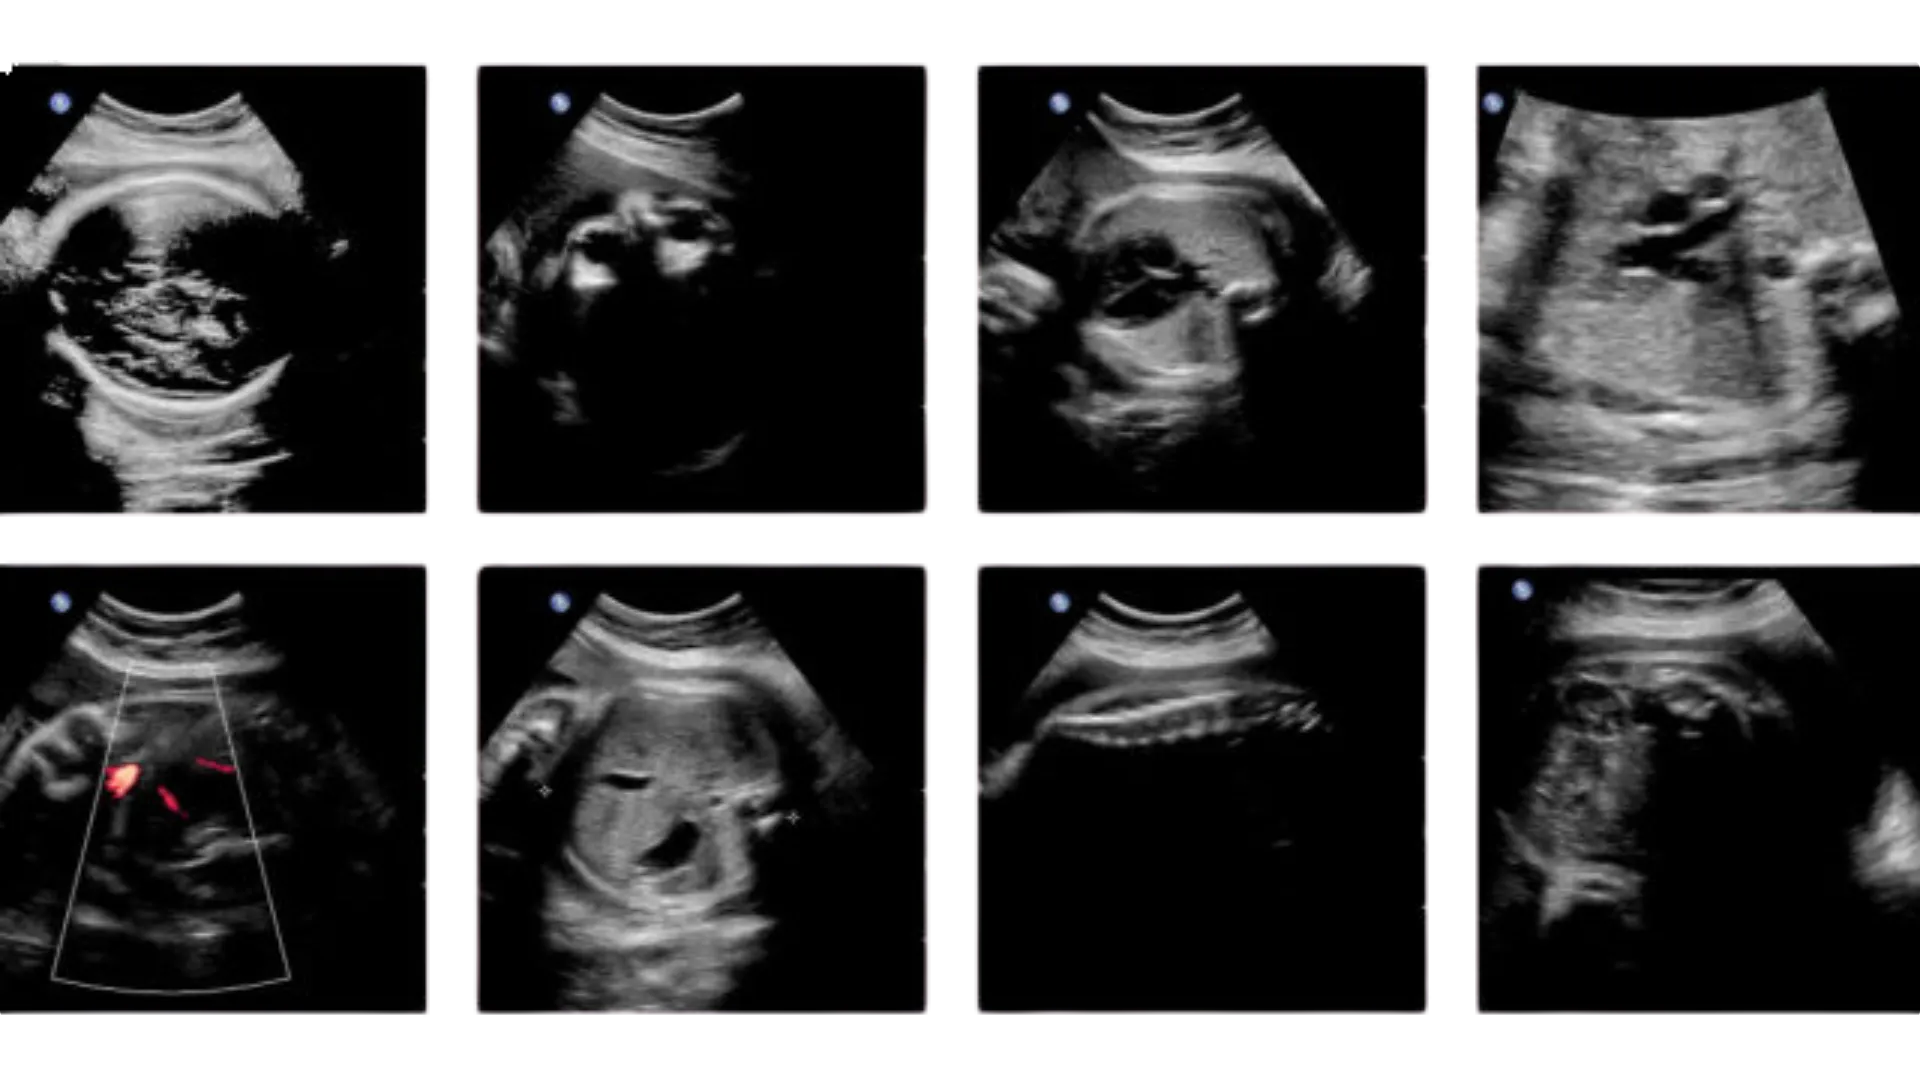

L’ecografia del 2° trimestre viene chiamata morfologica proprio perchè mirata principalmente ad analizzare la morfologia del feto, per:

- controllare la vitalità del feto;

- osservare l’anatomia del feto;

- controllare lo sviluppo del feto.

Inoltre valuta la quantità di liquido amniotico, la localizzazione placentare e il sesso del nascituro.

L’ecografista osserva il feto con la maggiore attenzione possibile, visualizzando di norma i seguenti organi interni:

- Cervello e Cervelletto;

- Faccia con osservazione del profilo, delle labbra e delle lenti del cristallino oculare;

- Colonna vertebrale;

- Torace con osservazione dei polmoni e della posizione del cuore;

- Cuore con studio delle 4 camere cardiache e aorta;

- Diaframma;

- Addome con controllo della chiusura della parete e studio degli organi interni quali lo stomaco, la colecisti, il fegato e l’intestino, apparato genito-urinario, con visualizzazione dei reni, della vescica e dei genitali esterni;

- Cordone ombelicale con la visualizzazione dei tre vasi che lo compongono e l’inserzione in addome ed in placenta;

- Arti superiori ed inferiori, ossa lunghe, asse delle mani e dei piedi, dita delle mani.